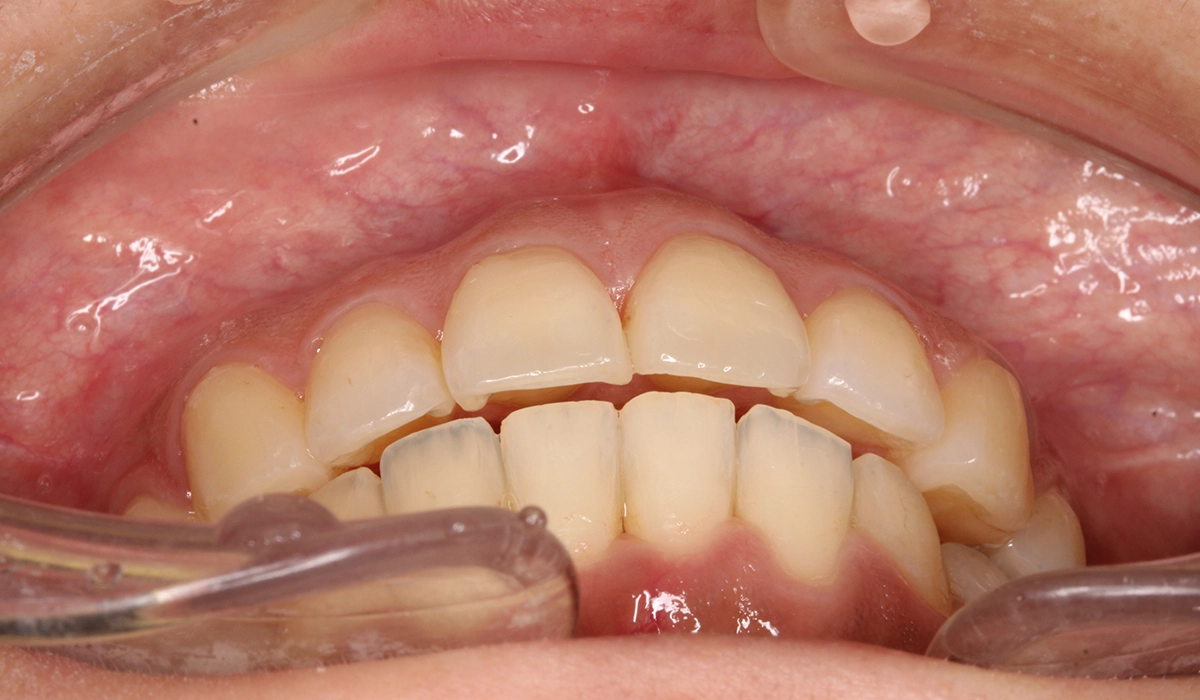

術前:正面

術後:正面